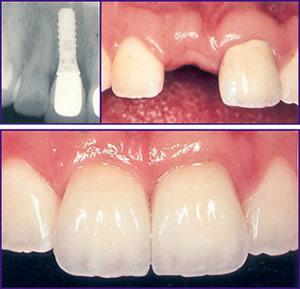

single tooth implant in Dubai UAE

Dental implants are suitable for most adults, regardless of how many teeth have been lost . the treatment can be carried out for a person who has lost one, a few or all of their teeth. A ceramic crown can be fixed by implanting into your gum the root of an artificial tooth – a dental implant that fuses to your jawbone.

The dental implant and crown become the permanent replacement for a missing tooth.